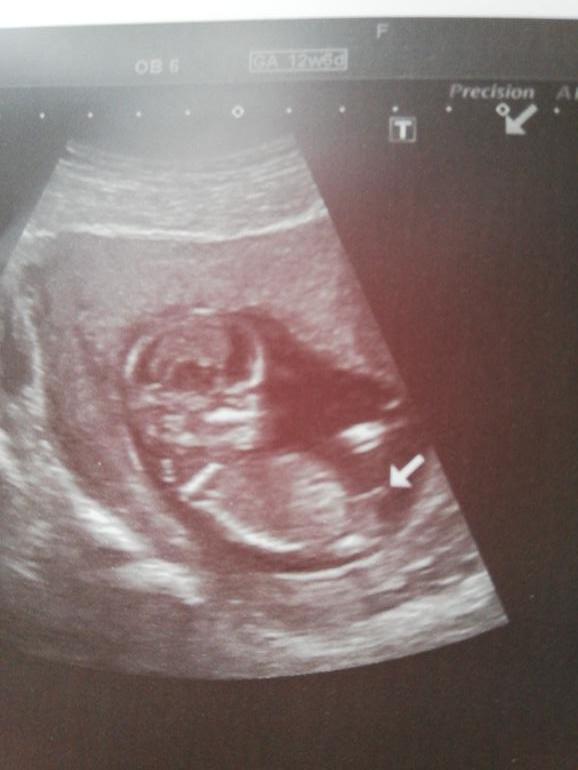

Девочки, подскажите пожалуйста. Сегодня была на узи. Врач сказал, что скорее всего мальчик. Но эта его неуверенность меня смутила. Любопытство мучает меня.)) срок 12 нед и 4 днЯ